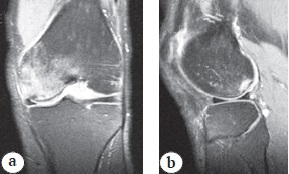

Patients of the main group (BMAC group) (n = 19) underwent a single intraosseous injection of BMAC in the area of bone marrow edema, whereas PRP (PRP group) was used in a similar procedure in the comparison group (n = 21). The zone of overload bone marrow edema and its localization were preliminarily determined according to MRI data and transposed to fluoroscopic images obtained during manipulations. Overload bone marrow edema was distinguished from aseptic necrosis by a change in the signal from the bone, which was characterized by low intensity on T1-weighted images and high intensity on T2-weighted images and short modes. Contrarily, the pathognomonic sign of aseptic necrosis was a line of low signal intensity along the periphery of the infarction focus with a bright inner line along the infarction surface on T1- and T2-weighted images. Foci of aseptic necrosis were predominantly located in the subchondral zone of the posterior-inner condyle parts of the femur and (or) tibia (Fig. 1, 2).

Fig. 1. MRI picture of the aseptic necrosis zone of the femoral condyle intero-posterior compartment in T1 mode: a — coronary section; b — sagittal section